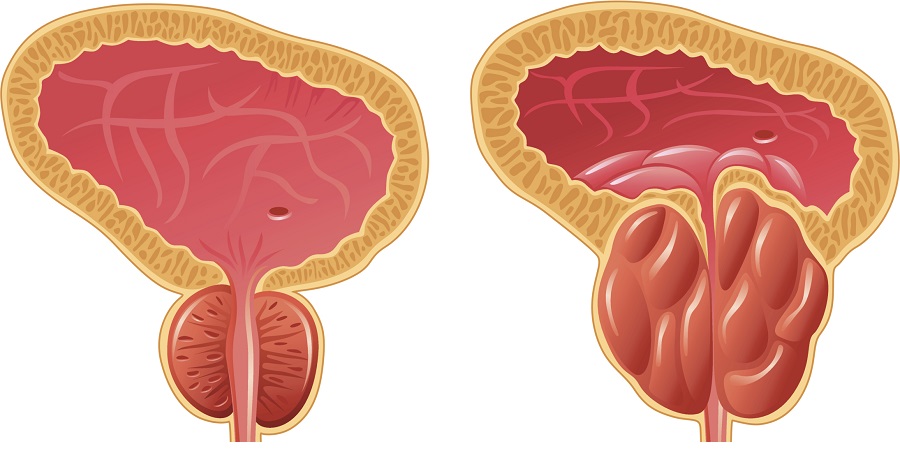

-Καλοήθης υπερτροφία του προστάτη

Στους άνδρες συμβαίνει στο εσωτερικό μέρος του προστάτη που περιβάλλει την ουρήθρα και συμβαίνει με την ηλικία, όταν υπάρχουν οι όρχεις. Εμφανίζεται στα 50 έτη σε 9 στους 10 άνδρες. Η διόγκωση του προστάτη γίνεται αργά και σταθερά, λόγω μείωσης του μονοξειδίου του αζώτου και αύξηση του οξειδωτικού στρες, που μπορεί να προκληθεί από χρόνια μόλυνση και διατροφικές ανεπάρκειες και από την φυσιολογική κυτταρική ανάπτυξη. Τα συμπτώματα της καλοήθους υπερτροφίας προστάτη είναι η επιτακτική, συχνή ανάγκη για ούρηση, η αίσθηση μη ικανοποιητικής κένωσης της ουροδόχου κύστεως, το κάψιμο στην ούρηση, η απώλεια ούρων και η νυχτερινή ούρηση. Αν έχετε υπερτροφία του προστάτη δεν υπάρχει κίνδυνος για καρκίνο του προστάτη, αλλά θα πρέπει να ελαττώσετε τα διουρητικά, όπως τον καφέ, γιατί επιδεινώνονται τα συμπτώματα, ιδίως το βράδυ. Οι σκύλοι αναπτύσσουν υπερτροφία του προστάτη στις εξωτερικές περιοχές του προστάτη και υποφέρουν από φράξιμο του ορθού και όχι της ουρήθρας και έχουν συμπτώματα από το έντερο.